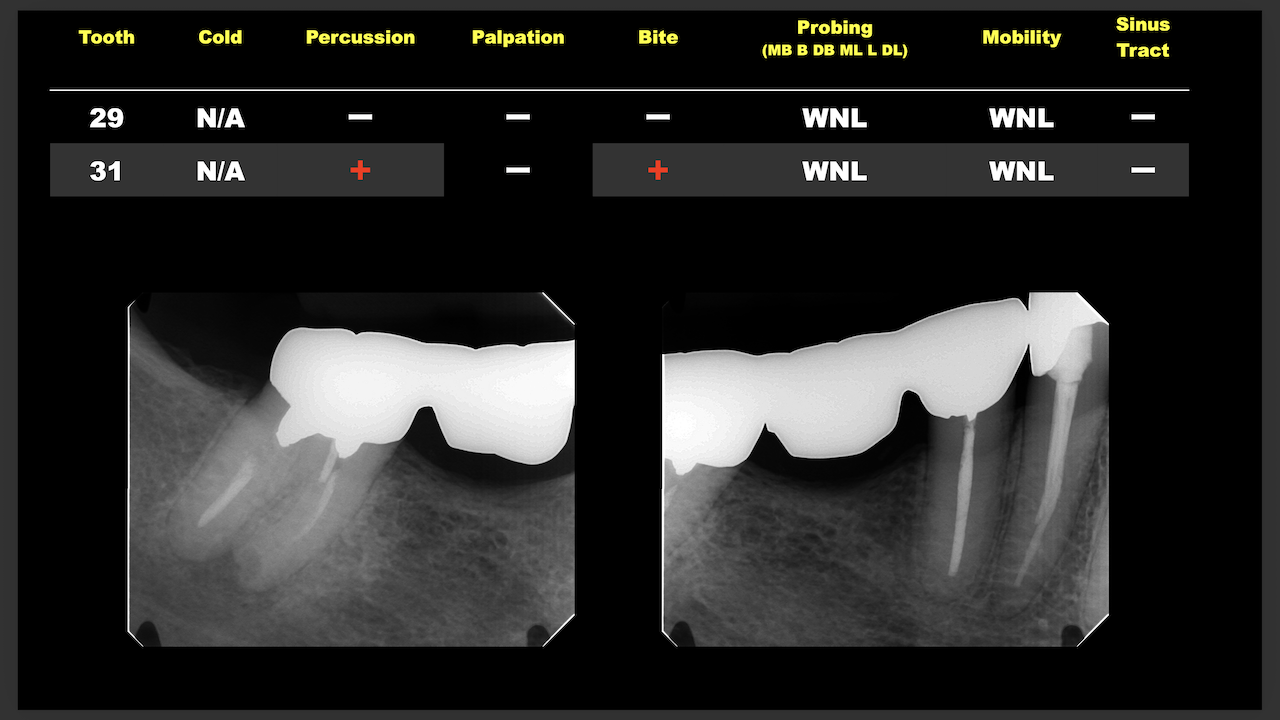

次はN先生と同一法人のF先生。

#10のRCTと3M recallである。

#9,10と病変があるが、

#9はColdに2秒で反応し、その痛みが5秒でおさまったことから生活歯と判断し、

Cold, EPTに反応がなく打診痛もある#10を患歯と考え、#10のみ根管治療することとなった。

その際の成功率は86%である。

と術前に患者さんに告げて治療へ導入し以下のようになった。

3ヶ月しか経過していないが根尖病変は大きく減少した。

治療していない#9には変化があまりないがだからと言って手をつける必要性はない。

患者に症状がないからだ。

先生も診断の重要性を学ばれたと思います。

これからも頑張ってください。